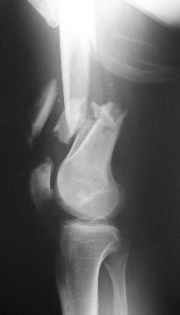

Отправитель: Zsolt Balogh 31 Октябрь 2004, 12:13

This is what we have done... As generally true for LISS look at the bone not the hardware.

There are two more srews above. The one not completely in got damaged head.